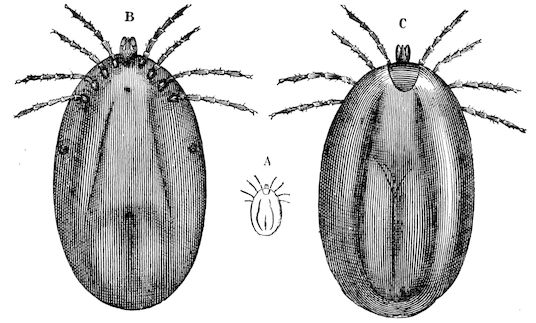

| Scabies—Scab—Mange | 611 | |||

| Scabies in sheep | 611 | |||

| Sarcoptic scabies | 612 | |||

| Psoroptic mange—Sheep scab | 614 | |||

| The tobacco-and-sulphur dip | 626 | |||

| Lime-and-sulphur dips | 627 | |||

| Arsenical dips | 632 | |||

| Carbolic dips | 633 | |||

| Chorioptic mange—Symbiotic mange—Foot scab | 636 | |||

| Mange in the ox | 638 | |||

| Sarcoptic mange | 638 | |||

| Psoroptic mange | 639 | |||

| Chorioptic mange | 640 | |||

| Mange in the goat | 641 | |||

| Sarcoptic mange | 641 | |||

| Chorioptic mange | 642 | |||

| Mange in the pig | 642 | |||